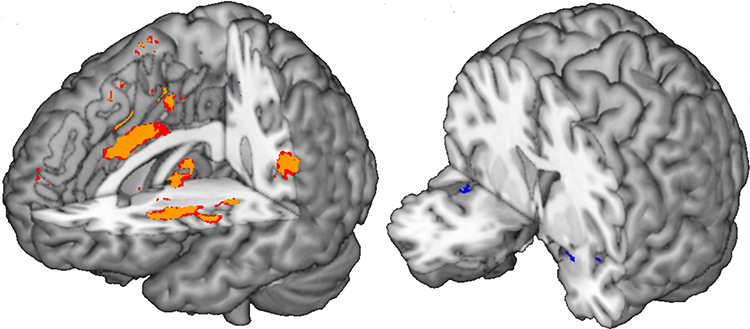

Partie du cerveau humain contribuant le plus à la prédiction de la douleur (aires oranges à gauche) et du dégoût olfactive (petites aires bleues à droite). ©UNIGE/Corradi-Dell'Aqua.

Les comportements malsains déclenchent des jugements moraux proches des émotions de base utiles à notre capacité de survie. Deux postulats différents existent dans la littérature scientifique actuelle quant à l’identité de ces émotions. Certains optent pour le dégoût, les autres pour la douleur. En développant une nouvelle approche d’imagerie cérébrale, une équipe de recherche de l’Université de Genève (UNIGE) a pu trancher pour le dégoût. L’étude, à découvrir dans Science Advances, montre que les comportements malsains enclenchent des réponses cérébrales similaires à celles provoquées par les mauvaises odeurs et identifie pour la première fois un biomarqueur cérébral du dégoût.